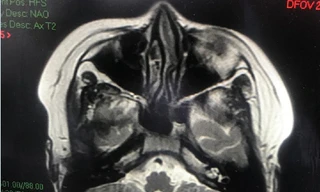

Từ khóa: "tổn thương não"